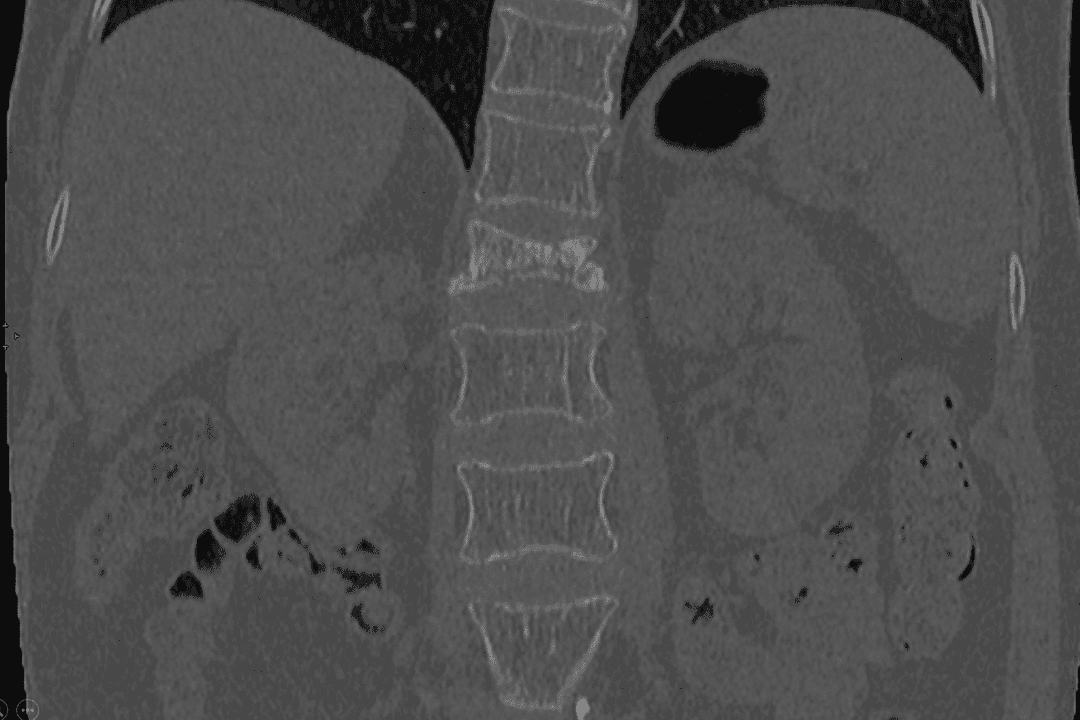

Scanner

Scanner montrant une fracture d'une vertèbre